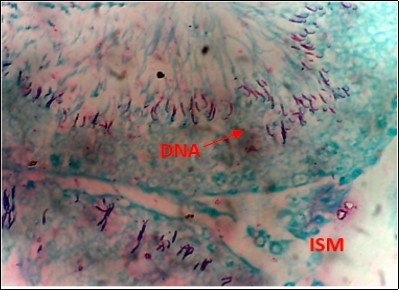

Figure 5.DC+250mg/kg.bw of AP X400 – Section of testis showing scanty DNA deeply stained with magenta color. DNA strands are in clusters

Figure 6.(DC+500mg/kg.bw of AP) X400 – Section of testis showing scanty DNA deeply stained with magenta color. DNA strands are in clusters

From findings in this study, irregular and distorted arrangements of DNA in all diabetic groups (Groups B, C, D, E and F) when compared with the normal control group, may have been due to displacement of sertoli cell within the germinal epithelium of seminiferous tubules. Strands of DNA were also seen arrange in clusters in diabetic groups, showing altered and defective structure which might have resulted from base free side deletion, frame shift, cross-linking and chromosomal rearrangement. The intensity of magenta colour development in Feulgen reaction for DNA demonstration was proportional to DNA concentration. There was reduced colour intensity in all diabetic groups (Groups B, C, D, E and F) when compared with the normal control. This is in line with report from Aitken and Krausz (2001). However the degree of distortion and cross-linking of DNA strand in the group of diabetic animal models placed on high dose (1000mg/kg.bw) of A. polytricha which may be a sign of amelioration. Groups C, D and F placed on 250mg/kg.bw A. polytricha, 500mg/kg.bw A. polytricha and standard anti-diabetic drug (metformin) respectively did not show remarkable differences in terms of DNA arrangements when compared with the diabetic control group. Groups D (500mg/kg.bw A. polytricha) and group E (1000mg/kg.bw) showed visible improvement in magenta colour intensity when compared with the diabetic control group.